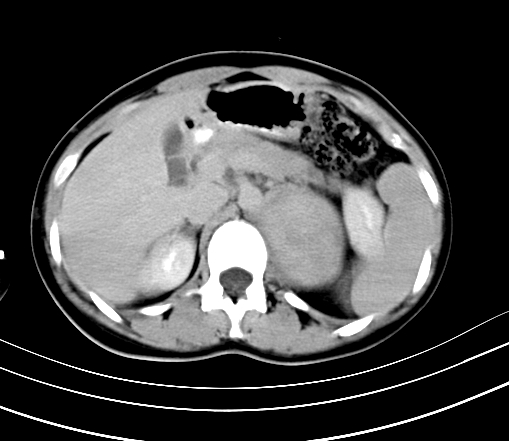

腹部平扫